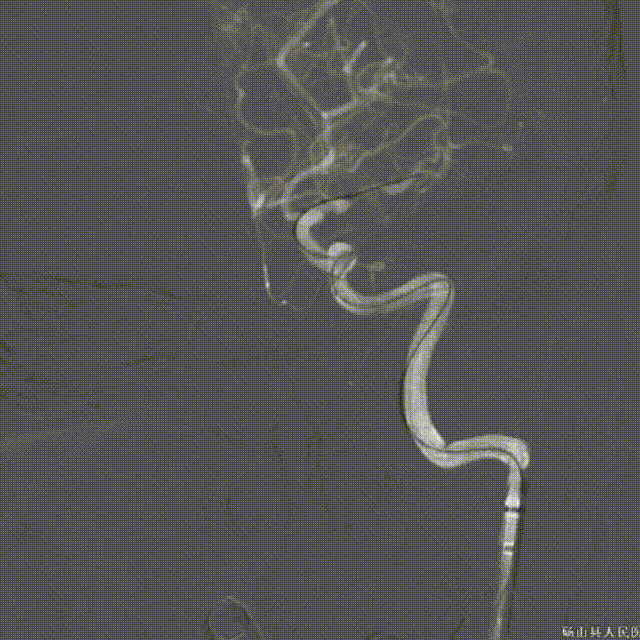

➤经股动脉入路造影影像

II型弓,左侧大脑中动脉M1段重度狭窄(几近闭塞)。

➤手术过程

微导丝带领微导管通过左侧大脑中动脉狭窄段。

微导管冒烟证实在血管真腔内。

沿微导丝将赛诺NOVA®颅内药物洗脱支架 2.5*15mm送至左侧大脑中动脉狭窄段,造影定位准确。

缓慢扩张球囊/释放支架。